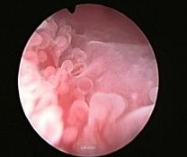

子 宫内膜炎怎么治疗有效

子 宫内膜炎是怎么造成的